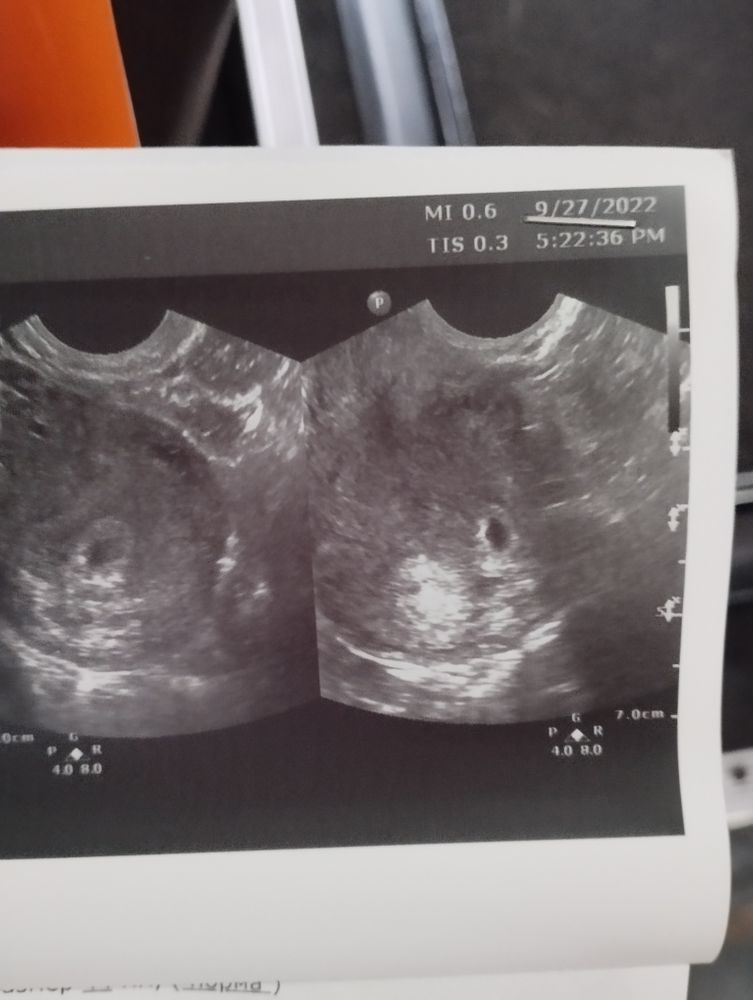

Беременность после внематочной: положительный случай 🥰

Господи, как же я боялась сегодняшнего УЗИ. Срок 4 недели 5 дней (акушерских), и не выдержала, побежала к врачу.

Нашли моё плодное яйцо! ❤️🥰

Овуляция произошла с оперированной трубы, скорее всего!) Так как желтое тело слева. А я хотела, чтобы отрезали второй раз, так как в основном говорят трубы не рабочие после вмешательств! Слава богу, у врачей своя голова и всё сохранили мне!) Понимаю, впереди ещё долгий путь вынашивания, но сам факт!

Беременность наступила! Она в матке ❤️